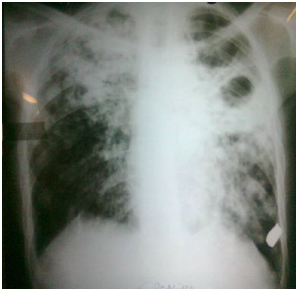

O atual sistema de classificação dos CDC para adolescentes e adultos infectados pelo HIV relaciona os indivíduos com base nas afecções clínicas associadas à infecção pelo HIV e contagem de linfócitos T CD4+. A categoria A consiste em infecção assintomática, aguda ou linfadenopatia generalizada progressiva, a B em estados sintomáticos não A e nem C, e a categoria C que inclui as doenças indicadoras de AIDS. Analise a seguir a radiografia de um paciente com células CD4+ menor que 200/ul.

São afecções pulmonares indicadoras de AIDS, EXCETO: